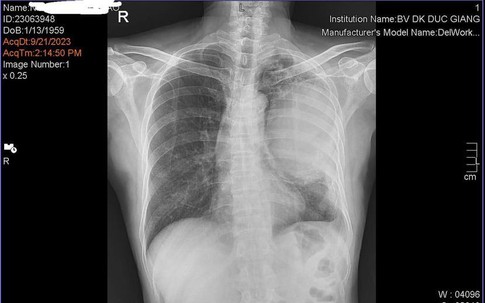

GiadinhNet - Gần đây thấy triệu chứng tức ngực, khó thở, người mệt mỏi, anh Hùng đi khám và được biết có u ác tính ở phổi.

GiadinhNet - Ung thư phổi là nguyên nhân tử vong hàng đầu ở cả nam và nữ. Năm 2020, có hơn 26.000 người Việt mắc mới bệnh này.

GiadinhNet – Hiện có rất nhiều yếu tố gây các bệnh lý đường hô hấp, ung thư phổi. Để bảo vệ lá phổi và biết lá phổi “sạch”, chuyên gia chia sẻ những lưu ý dưới đây.

GiadinhNet - Thông tin cậu bé 12 tuổi mắc bệnh ung thư phổi khiến nhiều người choáng váng, vì theo các bác sĩ, đối tượng mắc căn bệnh này thường là nam giới độ tuổi 60, có thói quen nghiện thuốc lá…

Thấy ho ra máu tươi, ông Việt đi khám, được bác sĩ chẩn đoán mắc ung thư phổi giai đoạn cuối đã di căn hạch nhiều nơi.

GiadinhNet - Nhạc sĩ, nhà văn, nhà báo Vũ Đức Sao Biển - tác giả ca khúc "Thu hát cho người" vừa qua đời đêm qua sau thời gian dài chống chọi ung thư phổi.

Ung thư phổi là ung thư có tỉ lệ tử vong hàng đầu, mỗi năm cướp đi mạng sống gần 21.000 người Việt.